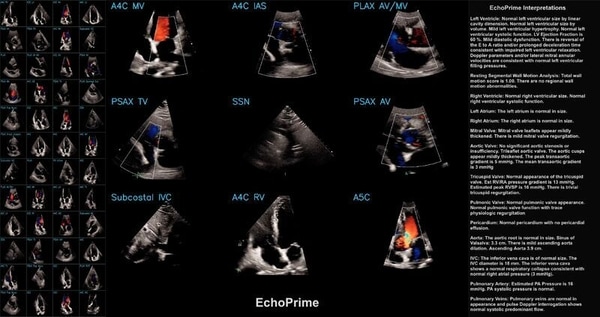

Cedars‑Sinai EchoPrime is a New AI-Accelerated Medical Tool

Cedars‑Sinai introduced EchoPrime, a video-based vision-language AI that analyzes echocardiogram footage and generates written cardiology reports, featuring training on over 12 million echo videos paired with clinician interpretations. The system was developed with collaborators at Kaiser Permanente Northern California, Stanford Health Care, Beth Israel Deaconess Medical Center and Chang Gung Memorial Hospital and was published in Nature in February 2026.

EchoPrime was evaluated across five international health systems and beat task-specific and prior foundation models on 23 benchmarks of cardiac structure and function; the team released the model’s code, weights and a demo to allow external testing. The model produces verbal summaries for clinician review rather than autonomous diagnoses and was trained on 275,442 studies from 108,913 patients.